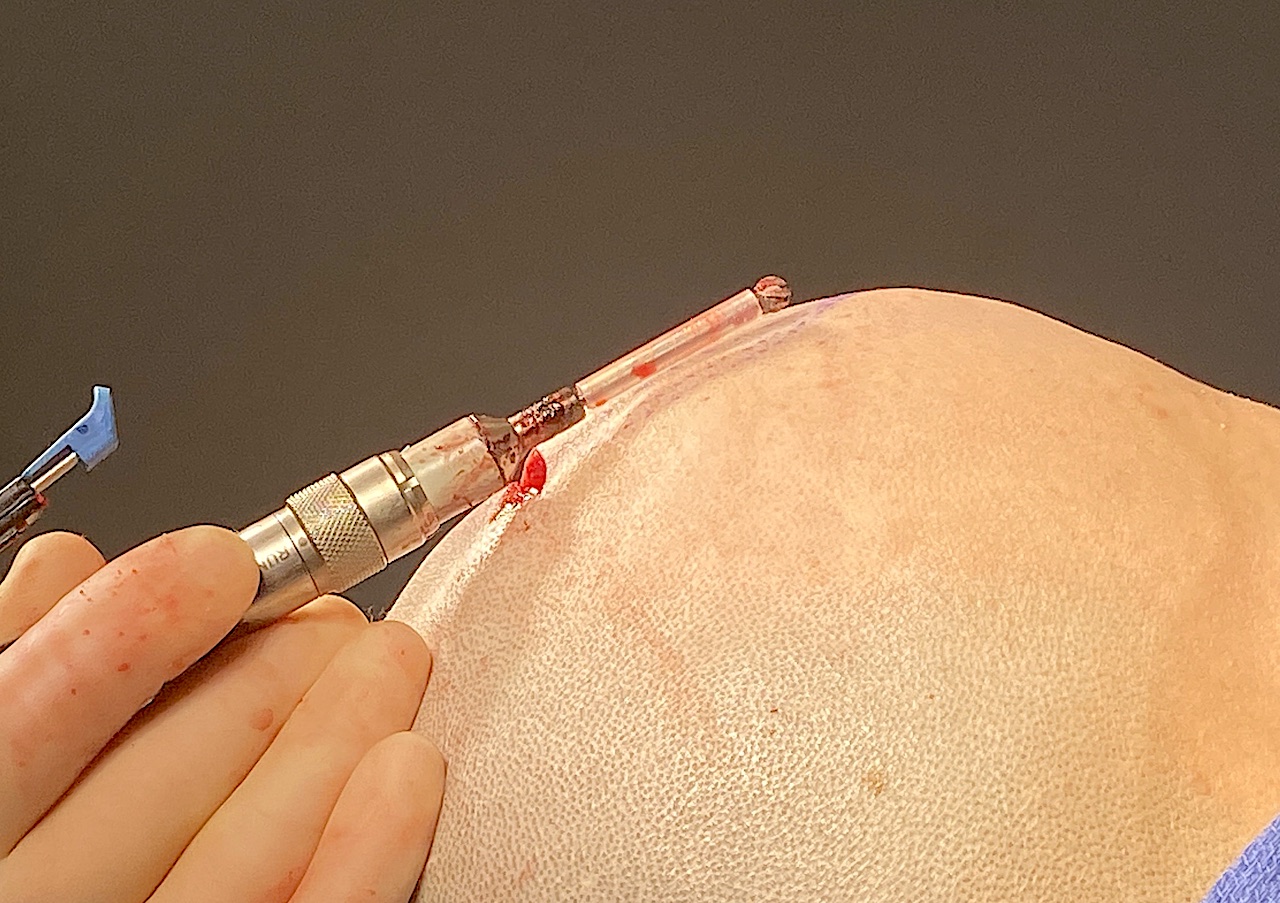

Desire for reduction of prominent occipital knob deformity.

Intraoperative result from occipital knob skull reduction through a direct small scalp incision.

Desire for reduction of prominent occipital knob deformity.

Intraoperative result from occipital knob skull reduction through a direct small scalp incision.